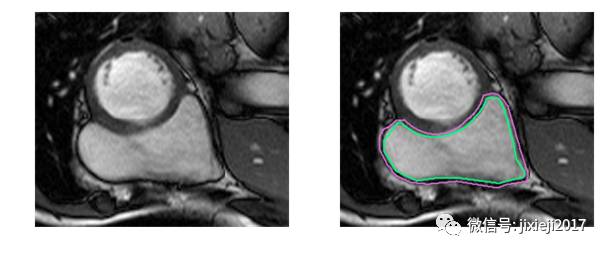

右心室在原始图像中几乎看不到,真实值的面积也相当小。将其与比较成功的分割比较:

或者简单的情况比较: